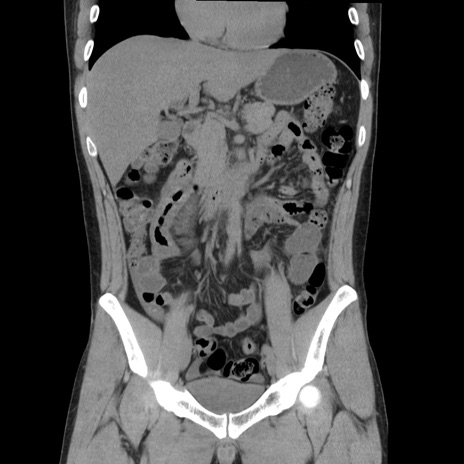

症例36(冠状断像)

【症例】20歳代 男性

【主訴】心窩部痛

【現病歴】今朝より上腹部痛あり。一旦軽快していたが再度出現したため救急要請。昨日夕に白身の魚を含む刺身を食べた。

【身体所見】BP 136/89mmHg、HR 74/min、BT 37.0℃、腹部:膨満、軟、心窩部に圧痛あり。反跳痛なし、筋性防御なし、腸雑音やや亢進あり。

【データ】WBC 17700、CRP 0.48